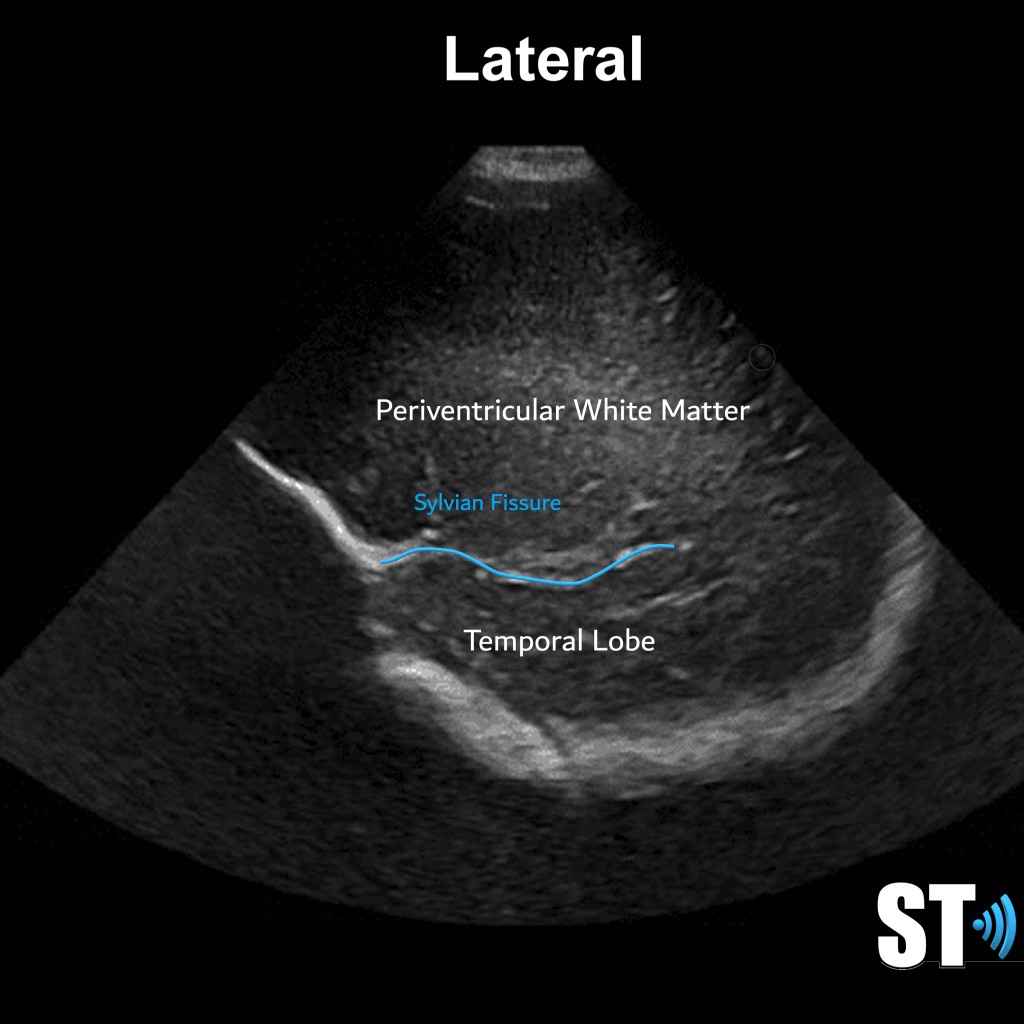

The Cerebrum is the most cephalad portion and consists of 4 lobes: frontal, parietal, temporal and occipital lobes. The separation of these lobes is by way of fissures, which are large grooves. Important ones that pertain to sonographic imaging are the sylvian Fissures, cingulate gyrus and the interhemispheric fissure, which divides the brain into right and left hemispheres.

Periventricular white matter should be less echogenic than the choroid plexus. The infant brain that is <32 weeks gestational age will have a smoother appearance with less sulci and gyri. 36 weeks and greater more sulci and gyri and the ventricles are more slit like.

- Periventricular white matter normally hyperechoic but < choroid plexus